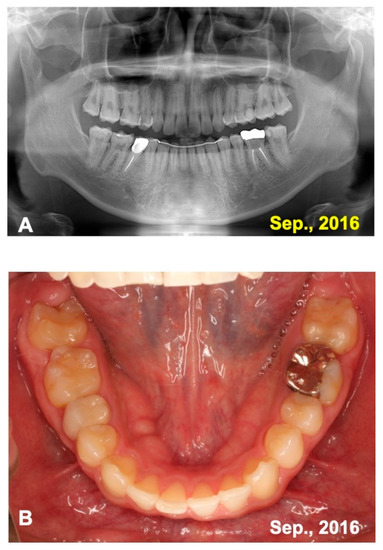

3.1. Gross View and Examinations after Surgery

3.2. Radiographic Evaluation